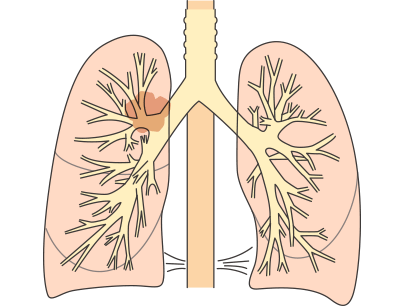

①肺がんの発生部位による違い

肺の入り口付近(肺門型肺がん):初期の段階から咳、痰や血痰などが発現します。

肺の奥(肺野型肺がん):初期に自覚症状はなく、進行して肺周囲の臓器に浸潤すると症状が現れます。

肺の中心にがんができる肺門型肺がんは、早期から咳や痰、血痰などの症状がでますが、肺の端のほうにがんができる肺野型肺がんでは初期症状はほとんどなく、進行期になって息切れや呼吸困難などがあらわれます。

肺がんと血痰の関係

肺がんはできた部位によって肺門型(肺の中心部にできたがん)、肺野型(肺の端にできたがん)に分けられ、型によって症状の出方が異なります。

肺門型の肺がんは気道に近い部位にでき、気道が刺激されるので、早期のうちから咳や喀痰、血痰があらわれることがあります。一方、肺野型の肺がんは気道から遠い部位にできるので、多くの場合、進行するまでは血痰はあらわれにくく、無症状で経過します。術後に血痰がでた場合は再発が疑われます。

その他、肺がんはがんの発生部位によって肺門型肺がんと肺野型肺がんに分けられます。

発生部位による分類

| 特徴 | |

|---|---|

| 肺門型肺がん |

|

| 肺野型肺がん |

|

肺門型肺がんと肺野型肺がん